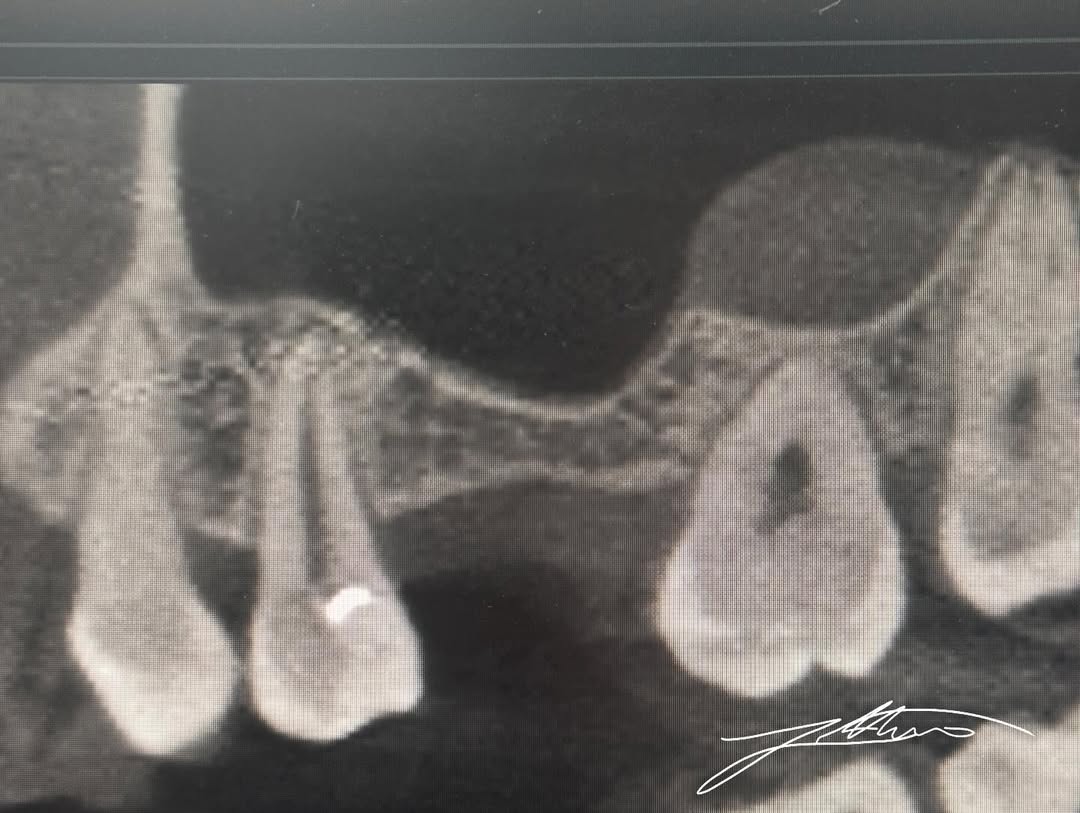

Ekzaminimi CBCT pas operacionit konfirmoi:

• Pozicionimin korrekt të implantit dentar

• Ngritjen e suksesshme të sinusit maksilar

• Integritetin e membranës së Schneider-it

• Karakterin atraumatik të procedurës së realizuar

Këto rezultate u arritën falë saktësisë së impulseve magneto-dinamike të Magnetic Mallet, të cilat lejojnë një transferim energjie shumë të shpejtë dhe të kontrolluar, pa krijuar trauma të panevojshme.